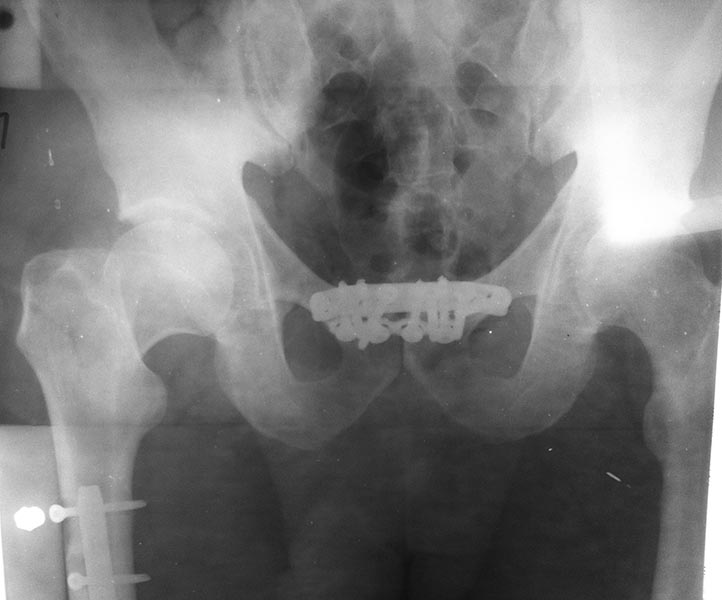

Представляю материалы по больному на сегодня. Сделали 13.03.2013г. снимки.

Действительно, ситуация несколько прояснилась, повреждение было APC III, необходимо было добавить IS винт. Сейчас: пластина с аппаратом или винтом.

Уважаемые коллеги! Спасибо Артуру Аслановичу и Александру Николаевичу за поздравления! Впечатляет масса различных мнений и советов, особенно ненавязчивые сомнения по поводу "проблемы" правого тазобедренного сустава. Мне тоже "кажется", однако эта проблема, безусловно, называется базальный перелом шейки правого бедра, что подтверждается измененным шеечно-диафизарным углом почти до прямого, нарушением линии Шентона и дуги Адамса. Учитывая время, прошедшее с момента травмы, молодой возраст пациента, нельзя исключить, что уже имеются признаки коснолидации, тогда, увы, будет необходима открытая репозиция с коррекцией смещений и фиксация (согласна с А.А.Волной) DHS.

Я бы обратил бы внимание на состояние правого тазобедреннего сустава. Возможно из-за проекции, но проксимальное бедро во внутренней ротации, укорочение и неправильная Шентон линия. Отдельный снимок тазобедреннего сустава или КТ.

Вы обратили внимание на межвертельный перелом или перелом шейки правой бедренной кости правой бедренной кости, кажется там еще есть укорочение, и смещ. отломков. Я бы обратил на это внимание. Может быть я ощибаюсь . Возможно у Вас есть КТ.